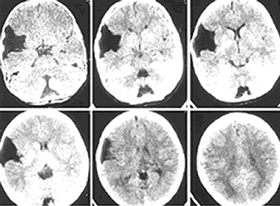

1、CT 掃描顯示邊緣光滑、輪廓清晰、無鈣化、位於腦質外類似腦脊液密度的囊性病變 , CT 值為 4 ~ 8Hu , 周圍無水腫帶 , 造影劑無強化效應。毗鄰腦組織受壓,但一般多無中線移位。一些特殊部位如鞍上、四疊體的病變壓迫室間孔或導水管時可致腦室擴大、腦積水改變。

蛛網膜囊腫術前(左)術後(右)對比蛛網膜囊腫患者的最佳治療方案仍有許多爭論。有觀點認為當患者無顱內高壓症狀或無神經系統定位損害時應保守治療,因為有部分患者在行手術探察或切除術後出現不能預知的惡化或死亡。主要是囊腫過份急速減壓使腦組織移位或出現術後感染、出血等嚴重併發症。也有觀點認為即使無症狀患者手術治療可以減少微小損傷導致硬膜下血腫的機率,兒童在無症狀時手術治療可以解除腦葉發育不全,腦組織代謝異常等囊腫對腦功能潛在的影響。當囊腫不斷增大引起顱壓增高或與之相關的腦積水、硬膜下血腫、神經定位損害、與囊腫相關癲癇發作,影像學提示腦組織壓迫時應考慮手術治療。手術治療的目的是解除壓迫。